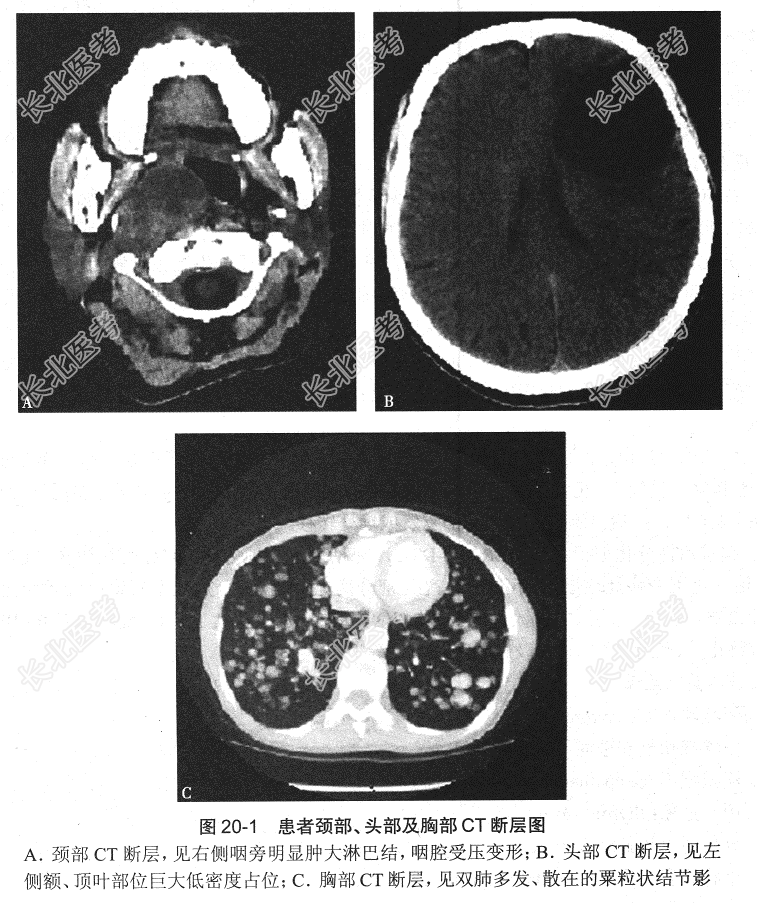

- [材料题] 患者女性,48岁,自诉36年前行“甲状腺右叶包块切除术”,术后病理结果提示为“甲状腺乳头状癌。术后患者未行¹³¹I治疗,病程中未定期随访及服用甲状腺激素替代抑制治疗。3个月前患者自感颈部再次出现多个肿大包块,伴胸痛、咳嗽、呼吸困难、头痛及头晕等不适,行头、颈及胸部CT检查,部分断层图见图20-1。